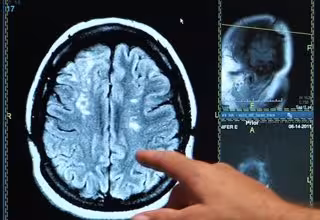

Vías cerebrales deterioradas pueden causar problemas de atención tras un accidente cerebrovascular

El daño a algunas de las rutas que transportan información por todo el cerebro puede ser responsable del déficit de atención en pacientes que sufrieron un accidente cerebrovascular subcortical en el hemisferio derecho del cerebro, según un estudio publicado en la edición digital de la revista 'Radiology'. Los investigadores esperan que los resultados puedan proporcionar una medida para seleccionar a pacientes adecuados para las intervenciones tempranas destinadas a reducir el deterioro cognitivo después del accidente cerebrovascular.

Un accidente cerebrovascular puede afectar a las regiones corticales de la corteza cerebral, que incluye la sustancia gris que recubre la superficie del cerebro, o puede afectar a las regiones cerebrales debajo de la corteza, incluidos los tractos de materia blanca que conectan diferentes regiones del cerebro. Un accidente cerebrovascular que afecta a las estructuras del cerebro por debajo de la corteza se conoce como un accidente cerebrovascular subcortical.

Más de un tercio de los pacientes experimentan deterioro cognitivo después de un accidente cerebrovascular, incluido el déficit de atención, que puede afectar y perjudicar la capacidad del paciente para llevar a cabo las actividades cotidianas de rutina.

Los resultados mostraron que, en comparación con los controles, los pacientes con accidente cerebrovascular crónico exhibieron un tiempo de reacción prolongado durante la tarea de atención. VLSM reveló que tener una lesión aguda de apoplejía en el núcleo caudado derecho y la sustancia blanca cercana se correlacionó con el tiempo de reacción prolongado. La TDT mostró que la lesión responsable estaba localizada en las vías prefrontal talámica y caudada derecha en los controles.

El subgrupo de daño cerebral derecho había disminuido significativamente la anisotropía fraccional (AF) en estas vías, que se correlacionaron con el tiempo de reacción prolongado. La AF proporciona una forma de medir la difusión que ocurre dentro de una región del cerebro y es típicamente más alta en regiones cerebrales de alta organización. Las reducciones en la AF se han asociado previamente con el avance de la edad y en casos de deterioro cognitivo.

"El deterioro de las vías prefrontales talámicas y caudadas correctas se asociaba sistemáticamente con el déficit de atención en pacientes con accidente cerebrovascular subcortical derecho --dice Yu-. Con base en esta asociación, se puede estimar qué pacientes con accidente cerebrovascular serían más propensos a tener déficit de atención persistente a largo plazo mediante la evaluación del daño inducido por la lesión a estas vías".